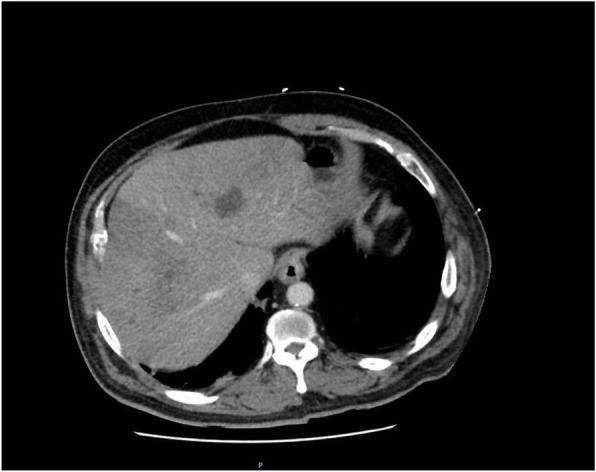

The patient’s condition significantly deteriorated over the next 24 hours, and he was admitted to intensive care with septic shock and renal failure. He required support with multiple inotropes and dialysis. Antibiotic cover was extended to include vancomycin, meropenem, and clindamycin (Table 2). Repeat CT of the abdomen and pelvis demonstrated small bowel enteritis, hepatic infarction, and portal vein thrombosis suspected to be septic thromboembolism. CT also demonstrated several hepatic hypodensities consistent with multiple abscesses, the largest measuring 41 mm in diameter (Fig. 2). Ultrasound-guided drainage was performed, and 35 ml of hemoturbid fluid was aspirated. The result of culture of the hepatic abscess was positive for E. avium.

Fig. 2.

Computed tomography (CT) of the abdomen and pelvis 72 hours after presentation to the hospital showing multiple lobulated intrahepatic collections, infarction of hepatic segments 5 and 8, and septic occlusion of the portal vein. There were no gas locules associated with the abscesses. CT also demonstrated small bowel enteritis (not shown)